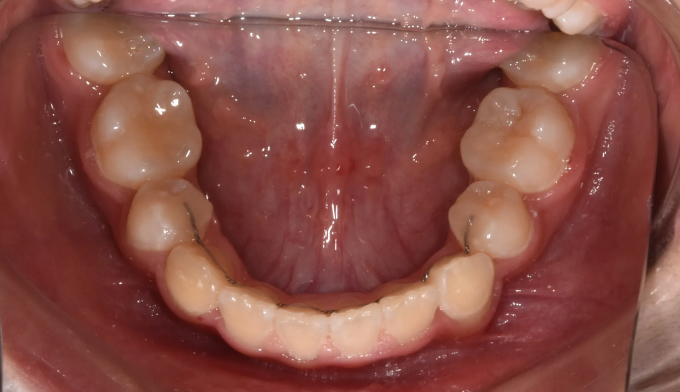

좁은 위턱을 확장하여 치아를 배열할 공간을 만들어주었고, 이 공간을 이용해 치아를 배열합니다.

아래턱의 과성장이 심해지고 있어서 절충치료로 아래치열을 배열해줍니다.

이미 송곳니와 작은어금니의 위치가 꽤 많이 바뀐 상태에서 치과에 내원하게 되어 어쩔 수 없이 최종적인 위치를 바꿔서 배열합니다. 씹거나 말하는데는 전혀 문제가 없습니다.

총 치료기간은 26개월 입니다.